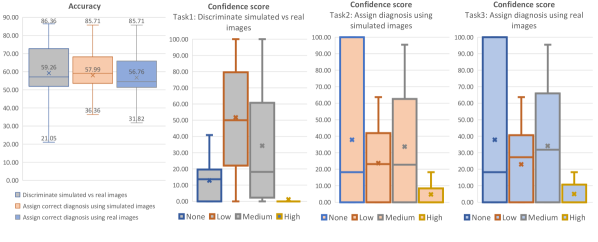

The results of this survey are presented in Fig. 8 where each task is represented with a different colour: i) bars in grey depict the results related to the discrimination task (real vs simulated images), ii) bars in orange depict the results related to the diagnosis using simulated images and iii) bars in blue depict the results related to the diagnosis using real images.

On the first left graph of Fig. 8, we can see that participants can discriminate the real and simulated images with an accuracy of 59.3%. We specifically noticed that neurologists achieved the highest accuracy (76.4% 2.6%), while neuro-radiologists obtained 68.0% 7.1%, neuroimaging experts 54.6% 18.6% and finally, medical imaging researchers 45.4% 6.4%.

These results show that even the most highly trained participants have some difficulty discriminating between synthetic and real images (best score was 86.4%), and all the participants together achieved just 59.3% of accuracy that is slightly worse than the ideal case of random choice when the 2 classes are indistinguishable.

In Fig. 8 we can also see that the diagnosis using synthetic images is almost identical to the real follow-up (57.9% vs 56.8%) supporting the idea that our system is able to capture key aspects of disease progression.

In terms of the confidence scores related to the discrimination task (second left graph in Fig. 8), the majority of experts have select a low or a medium confidence score, confirming once again that the images cannot be easily discriminated.

For the confidence scores related to the assignment of the diagnosis (last two graphs in Fig. 8), these are distributed equally between the none and medium confidence scores and we did not find differences between the results on simulated image and the real ones.

In Fig. 9 we report visual perception results from the survey of experts. These results show that the majority of the artefacts on the simulated images are minor noise/texture artefacts (31.6%) and minor morphological structural differences (29.3%). Only 2.6% were minor unrealistic artefacts, 2.6% major texture artefacts, 1.9% major structural differences, and 0% major unrealistic artefacts. From the results in this figure, we can also see that the simulated images have a slightly higher occurrence of artefacts with respect to the real images. In particular, in the last column, we can see that 30.5% of real images have at least one artefact against 49.6% for the synthetic images.

In conclusion, the highlights from our survey are as follows:

-

•

Simulated MRI scans contain minimal noise/texture artefacts and minor structural differences, approaching the levels of artefacts contained in real MRI scans.

-

•

Simulated MRI scans are diagnostically indistinguishable from real MRI scans.

-

•

Simulated images and real MRI scans are not easy to discriminate (average performance is 59.3%). However, experienced neurologists and neuro-radiologists were able to achieve reasonably high performance on this task (average 76.4%).